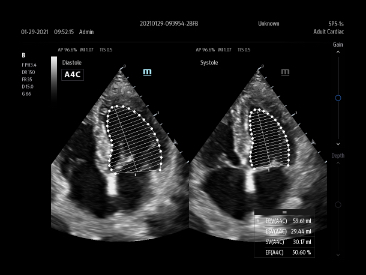

-Auto EF

One intelligent way to analyze 2D echo clips to automatically recognize diastole/systole frames and output EDV/ESV/EF etc. results by Simpson method.